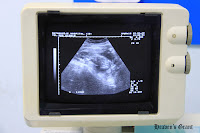

After discussing the result, Joyie was asked to make herself comfortable on the bed as the doctor checked the baby via ultrasound. It was really fun to watch the baby making little movements inside the womb. Everything's really fine and there is no signs of abnormality, Doctor Luetlak told us.